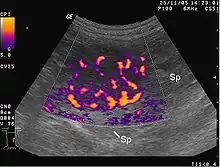

Les métastases sont souvent groupées, réalisant, lors des examens (radiographie de poumons, échographie hépatique, etc.), un véritable lâcher de ballons.